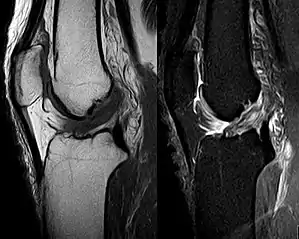

Injury

An anterior cruciate ligament injury results from excess tension on the ligament. This can come from a sudden stop or twisting motion of the knee. A few initial symptoms include swelling, knee instability, and pain. A popping sound or sensation may or may not be heard when the ACL first tears. A following symptom usually includes the feeling of the knee "giving out". Tearing of the ACL is the most significant injury because it leaves the knee unstable, which also causes the knee to lose its normal function.

The tear of meniscus is among the most common knee injuries. It is usually caused by torsional stress; twisting or turning of the knee too quickly with the foot planted on the ground while the knee is flexed. The feeling of a "pop" in the knee is usually felt when the meniscus is torn. Athletes, particularly those who participate in contact sports, are at a greater risk for meniscal tears. Sports-related meniscal tears often occur with other knee injuries, such as an anterior cruciate ligament tear.

A torn meniscus is commonly referred to as torn cartilage in the knee. Menisci tear in different ways and are noted by how they look, as well as where the tear occurs in the meniscus. Two types of tears include minor, which includes stiffness and swelling within two to three days but usually goes away in two to three weeks. Then there is severe, which without treatment, a piece of meniscus may come loose and drift into the joint space. Tears include longitudinal, parrot-beak, flap, bucket handle, and mixed/complex.